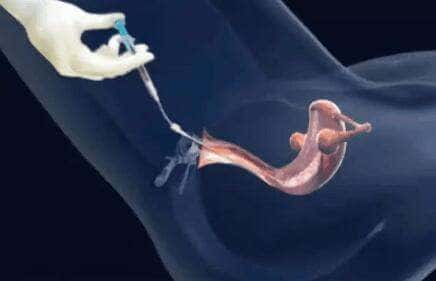

昨晚我们女士来移植咯,女士昨晚是从长春飞到曼谷的, 这一次女士是来移植了,我还记得促排的时候,是我亲自去素万机场接女士的呢,这么快就回来移植了,希望我们女士移植顺利...